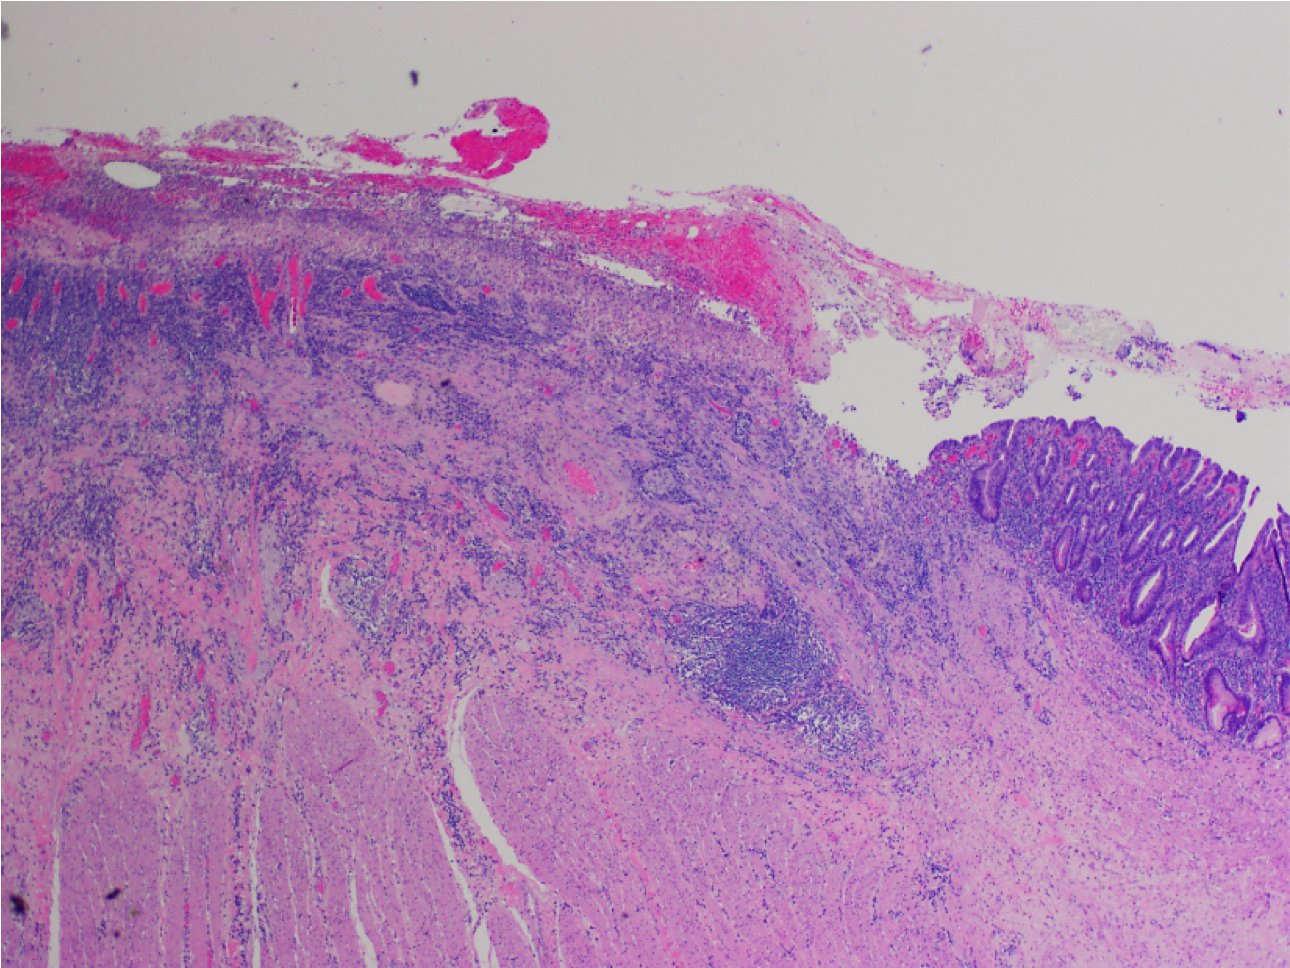

What’s this?

Gastric Ulcer

Mucosal denudation (left) with fibrinopurilent exudate (top), necrosis, and underlying granulation tissue.